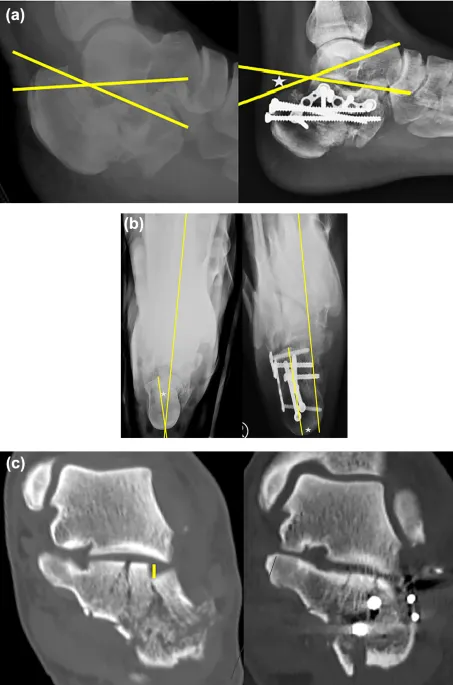

| CT Scan | Complex fractures | 95-99% | 95-99% | 10x | 5-15 mSv |

| Calcaneus | 20% | 80% | 4-5x | 70 MPa | 8-12 weeks |